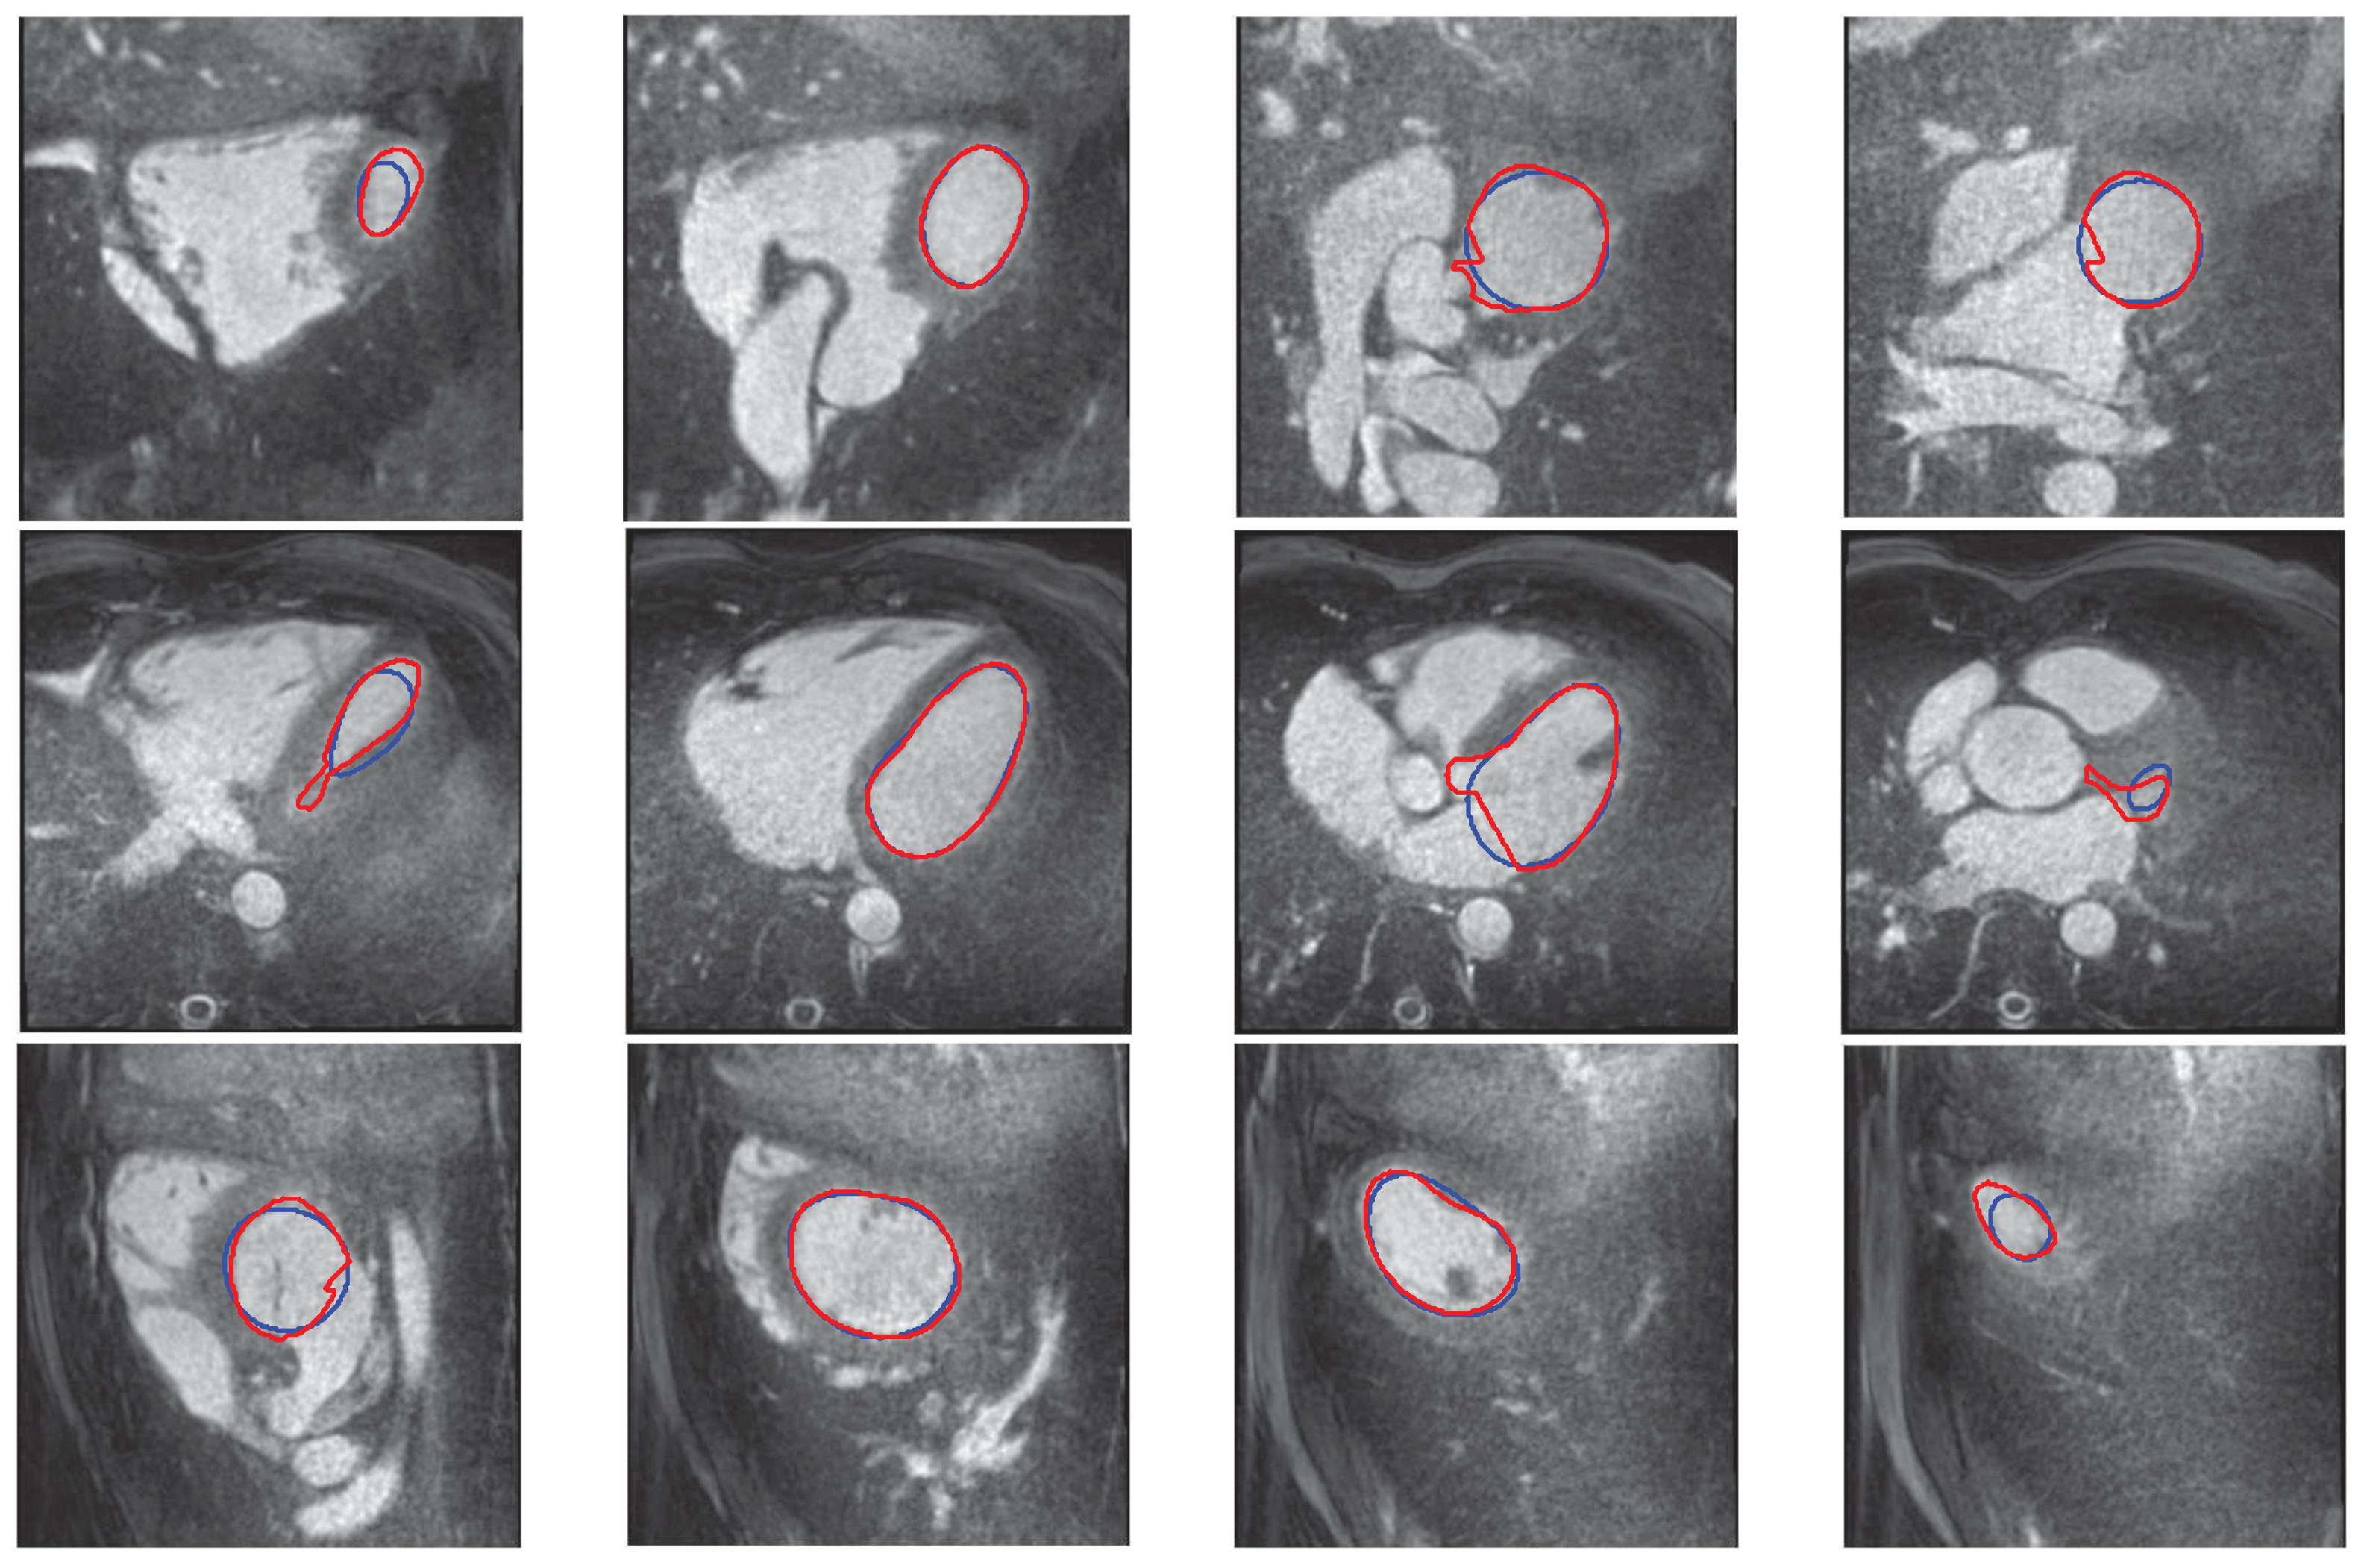

3.2. 3D Interpolation Evaluation